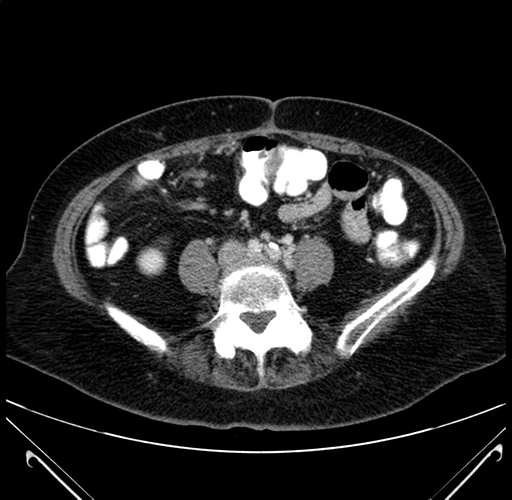

Pre-Chemo: Axial Venous

Axial Venous